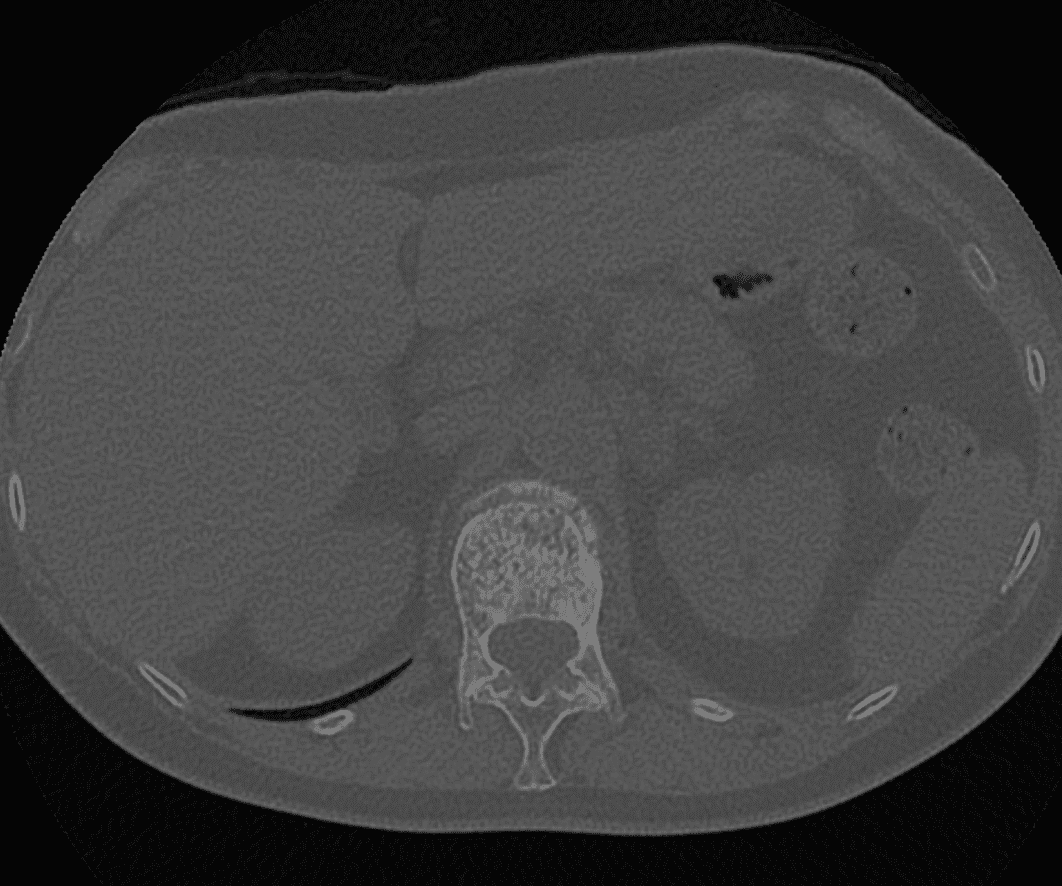

Guidage de l’aiguille

Grâce à des images en temps réel obtenues par fluoroscopie et/ou scanner, l’équipe médicale guide avec précision une aiguille jusqu’à la zone concernée, évitant ainsi les structures sensibles comme les vaisseaux sanguins.